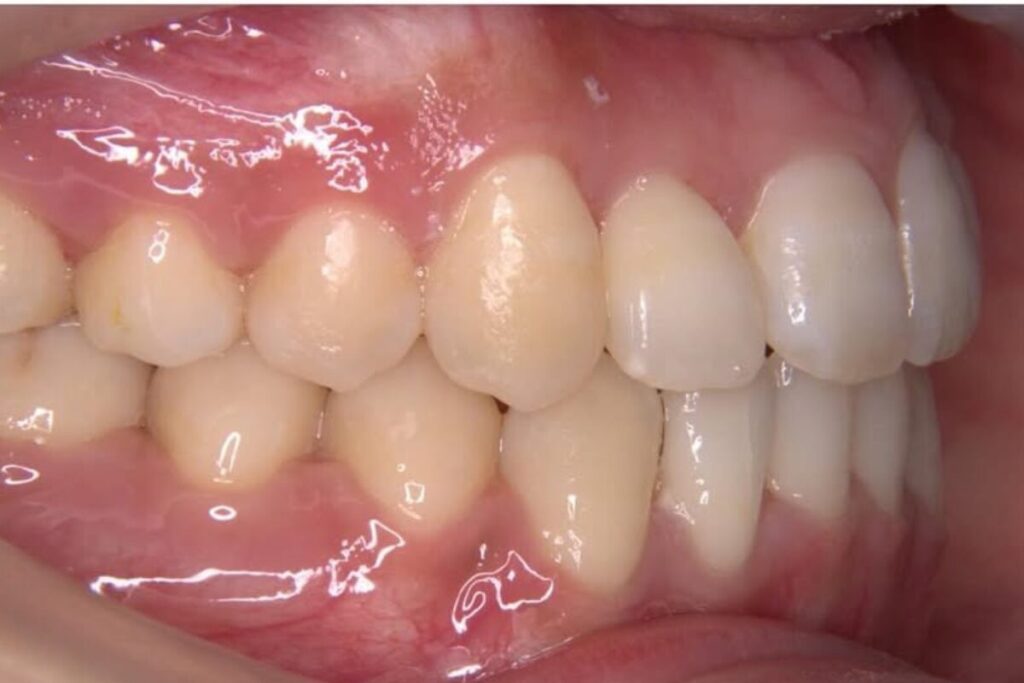

| 患者 | 28歳男性 |

|---|---|

| 主訴 | 歯ならびのガタガタ |

| 診断名 | UR7/LR7クロスバイトと上下叢生を伴うAngleⅠ級sk.1不正咬合 |

| 治療内容 | マウスピース型矯正装置(インビザライン)、部分的に上顎前歯部にワイヤー併用 |

| 抜歯の有無 | 非抜歯 |

| 治療期間 | 2年 |

| 費用(税込) | 594,000円 |

| リスクと副作用 | 痛み等、歯根吸収/歯肉退縮、後戻り、むし歯・歯肉炎の可能性。 |

【医師コメント】

上下のガタつきで来院された患者さんです。

精密検査の結果、UR7/LR7のクロスバイト(交叉咬合)と上下の叢生を伴う AngleⅠ級(sk.1)不正咬合 と診断しました。奥歯の前後関係はⅠ級で大きなズレは強くない一方、奥歯の噛み合わせのズレとスペース不足が原因でした。

治療はインビザラインを主体に非抜歯で計画し、歯列全体のバランスとかみ合わせの安定を意識しながら段階的に改善を進めました。

終盤、UL2のローテーションがわずかに残ったため、仕上げの精度を高める目的で上顎前歯部に部分的にワイヤーを併用しています。

治療は計画に沿って進行し、2年で歯列の配列とかみ合わせの改善を図ることができました。